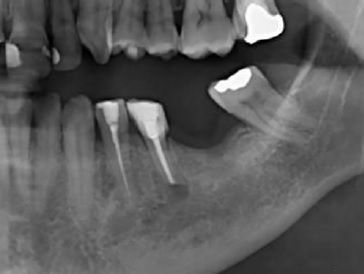

Ao exame radiográfico (Figura 2) foi possível identificar uma área radiolúcida unilocular, de contorno mal definido, na região periapical do dente 35, estendendo-se para o periápice do dente 34 e região edêntula correspondente ao 36. Para melhor visualização da extensão da lesão e sua relação com o canal mandibular foi realizada Tomografia Computadorizada de Feixes Cônicos. Cortes axiais e parassagitais mostraram rutura das corticais ósseas vestibular e lingual do corpo da mandíbula, além do íntimo contato da lesão com o canal mandibular (Figura 3), revelando o elevado risco de parestesia do nervo alveolar inferior e do seu ramo mentoniano, após intervenção cirúrgica.

Figura 2 Radiografia panorâmica inicial mostrando área radiolúcida unilocular, de contorno mal definido, na região periapical do dente 35, medindo aproximadamente de 1x2 cm, se estendendo para o periápice do dente 34 e região edêntula correspondente ao 36.